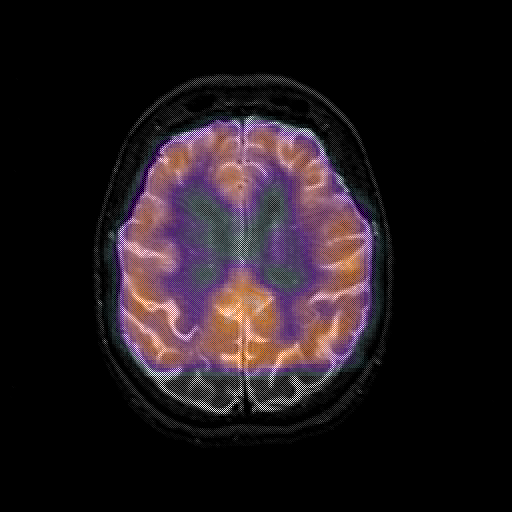

overlay 1: Slice 37

Slice 37

MRCBFCBF with

T1PDT2T1PDT2